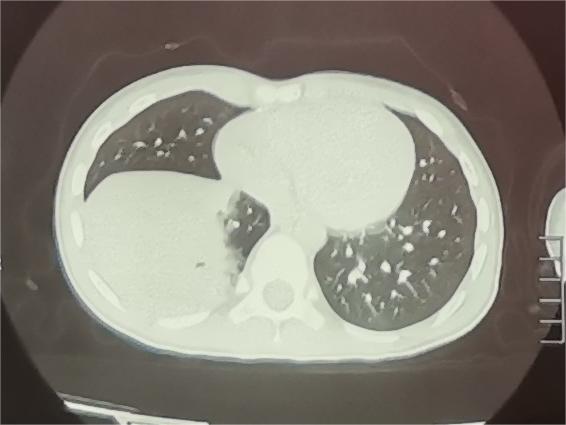

(图:肺炎支原体肺炎CT表现)

答案当然是“不一定”。是不是引起了肺炎还要结合孩子的临床症状、肺部听诊及肺部影像学情况,由专业的医务人员综合判断,肺炎支原体感染也可以仅仅表现为上呼吸道感染、支气管炎,不一定都会得肺炎。